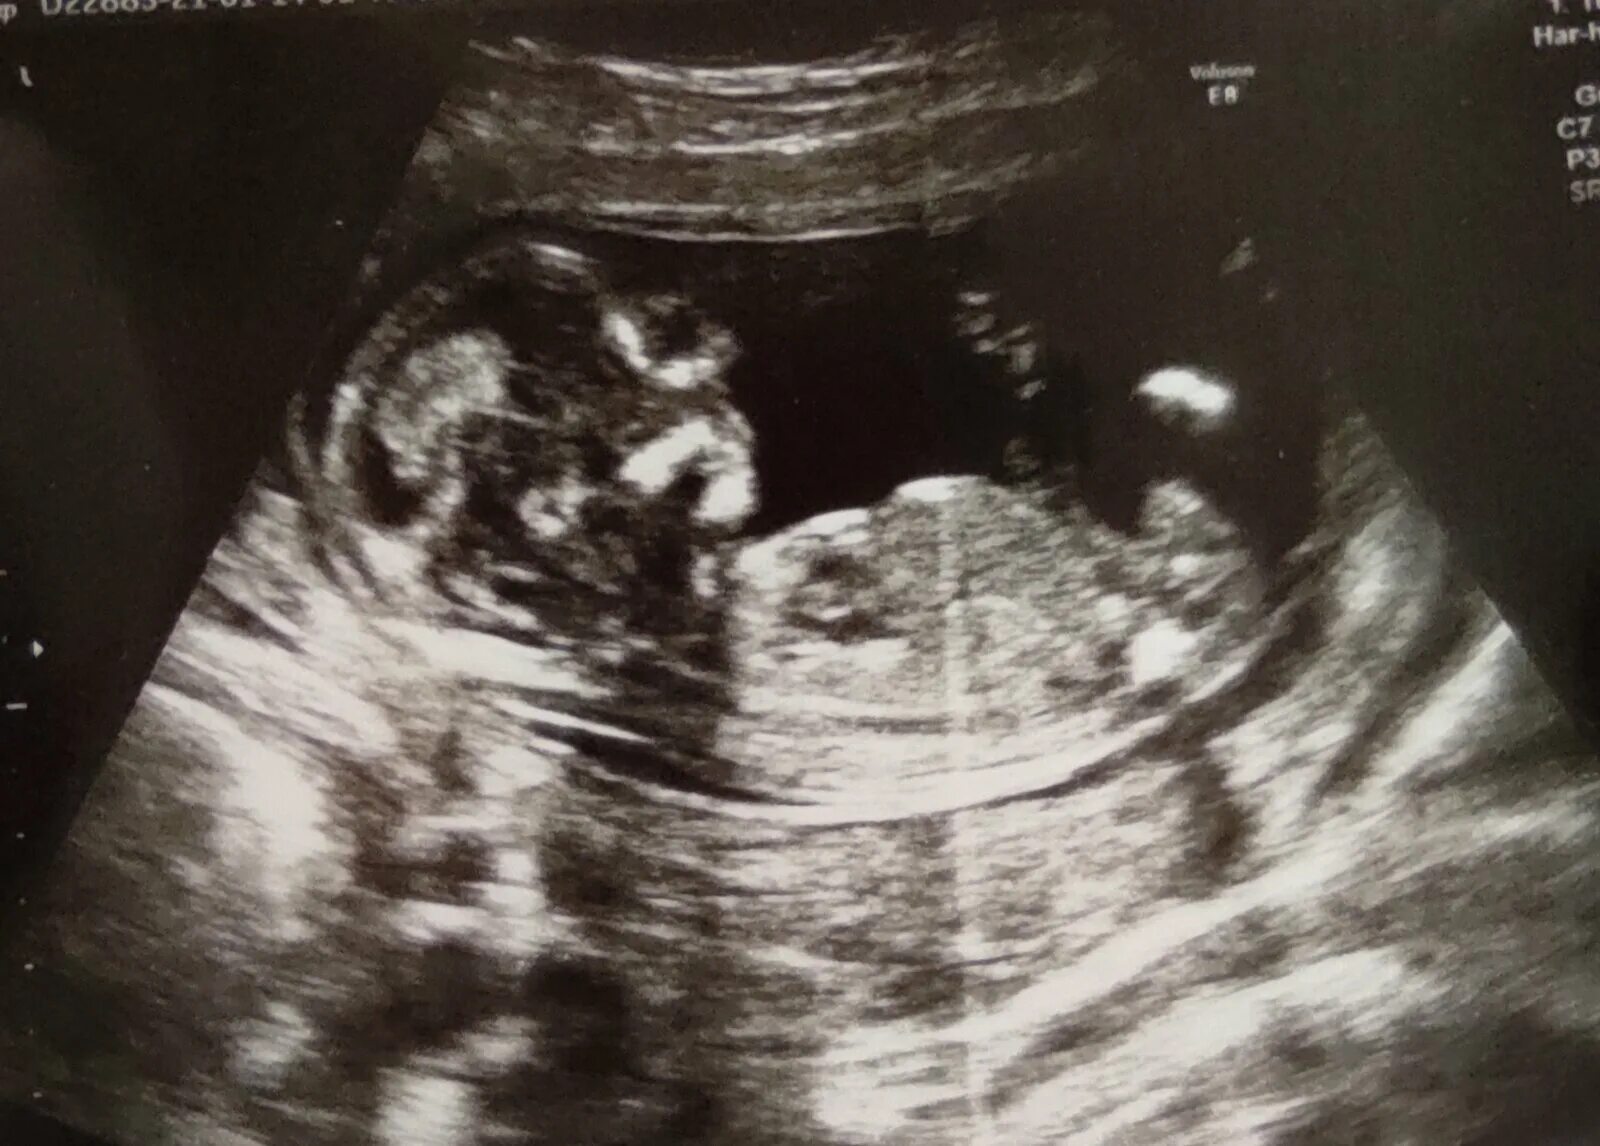

13 недель как выглядит малыш